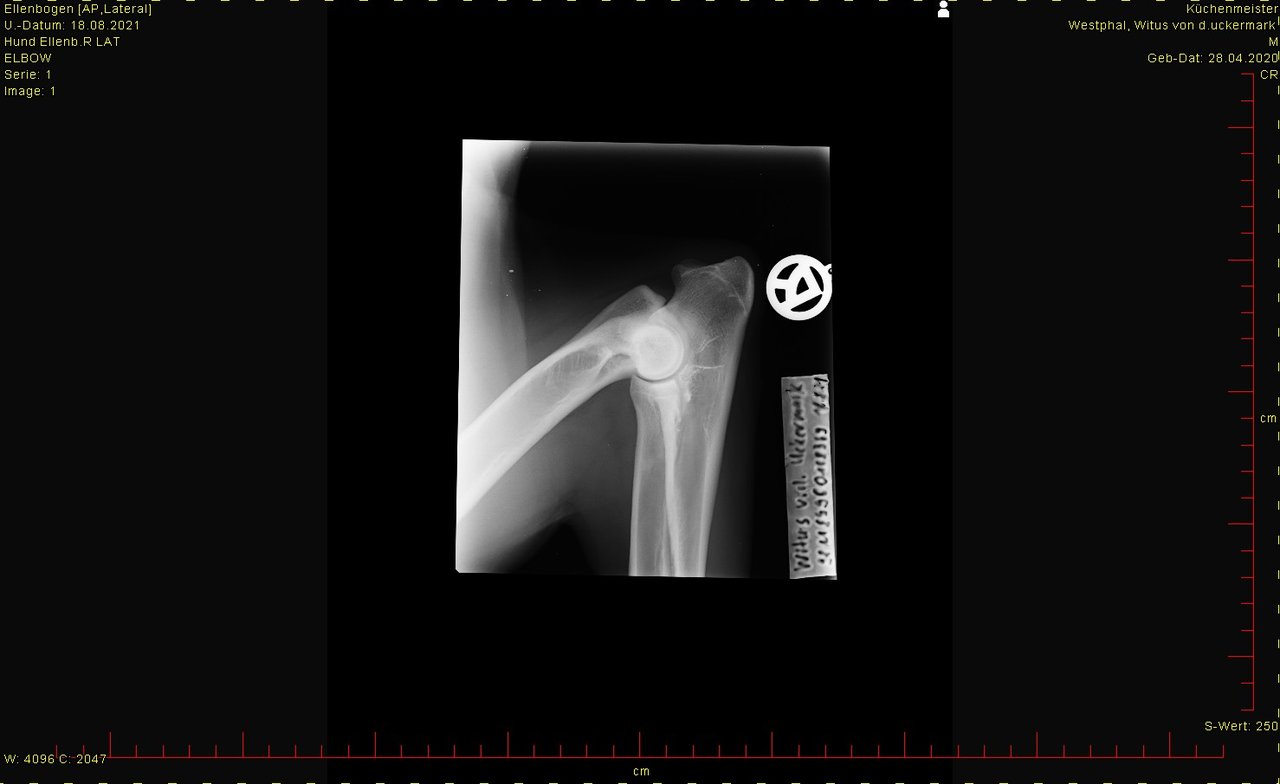

hier das Bild von der Hüfte. Ist HD-Aufnahme, kann man groß ansehen.

Was sagt Ihr dazu?

Aber weil Ihr ja die Bilder mal sehen wolltet hätte es ja sein können, das da jemand einen Blick für hat.

Bei den Ellenbogen traue ich mir keine Bewertung zu, finde aber, dass Hüfte und Rücken okay sind